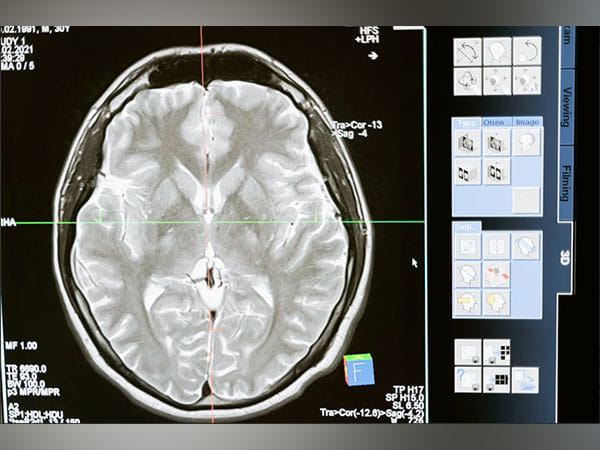

Brain waves, which are generated by synchronized neuronal activity, oscillate at different frequencies depending on what kind of task the brain is performing. When the brain is strongly engaged in mental activity, it produces higher-frequency beta (15-30 hertz) and gamma (greater than 30 hertz) oscillations, which are believed to help organize information and enhance communication between different brain regions.

Commonly used anaesthesia drugs such as propofol have a significant effect on these oscillations. During anaesthesia induced by propofol or other anaesthetics that increase the effectiveness of GABAergic inhibitory receptors in the brain, the brain enters a state of unconsciousness known as slow-delta-alpha (SDA). This state is characterized by slow (0.1-1 hertz), delta (1-4 hertz) and alpha (8-14 hertz) oscillations.

With higher doses of these anaesthetic drugs, the brain can fall into an even deeper state of unconsciousness. When in this state, known as burst suppression, EEG recordings from the brain show long periods of inactivity, punctuated by brief bursts of low-amplitude oscillations. When patients enter this state, they are more likely to experience postoperative confusion, delirium, and memory loss. These effects, which can last for hours, days, weeks, or months, are more common in elderly patients.

As the dosage of propofol was increased, patients showed two distinctive patterns of change in their EEGs. The first pattern was seen in the alpha waves, which started to wax and wane. As the dose increased, waxing was shortened and waning was prolonged, until the patient reached the state of burst suppression.

The researchers also found a distinctive pattern in the slow and delta waves seen in the patients’ EEG readings. Slow and delta oscillations are the slowest brain waves, and as the amount of drug was increased, the frequency of these waves became slower and slower, reflecting a decrease in brain activity.